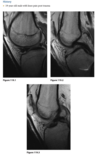

Sagittal proton-density (Fig. 2.14.1)

and fast spin-echo, T2-weighted fat-suppressed

(Fig. 2.14.2) MR images show an area of increased

signal intensity within the anterior cruciate ligament

(ACL), the so-called pseudo-mass (arrows); nonvisual-

ization of the normal ACL fibers; and a joint effusion.

A sagittal fast spin-echo, T2-weighted fat-suppressed

MR image through the lateral joint compartment

(Fig. 2.14.3) shows high-signal-intensity areas in the

subchondral regions of the midportion of the lateral femoral condyle and the posterolateral tibial plateau,

the so-called “kissing contusions”

Full thickness tear of the ACL

Conventional radiographic findings of an ACL

tear include avulsion fractures from the femoral or

tibial attachment of the ACL (Fig. 2.14.4, arrow), the

Segond fracture (Fig. 2.14.4, arrowhead), or a deep

lateral sulcus sign (Fig. 2.14.5, arrow).

MRI features of the torn ACL include an irregular

or wavy contour with decreased angulation on the

sagittal images (i.e., “lying down” or vertically ori-

ented ACL), increased signal intensity on all MRI

sequences in the region of the ACL (i.e., so-called

“pseudo-mass”), posterior displacement of the lateral

meniscus (i.e., “uncovered lateral meniscus” sign),

loss of the normal obtuse curvature with increased

angulation of the posterior cruciate ligament, undu-

lation of the patellar tendon, and the “empty notch”

sign, which is also seen on arthroscopy.

Bone

impaction from transient subluxation results in

the characteristic osseous contusions involving the posterolateral tibial plateau and midportion of the

lateral femoral condyle (i.e., “kissing contusions”).